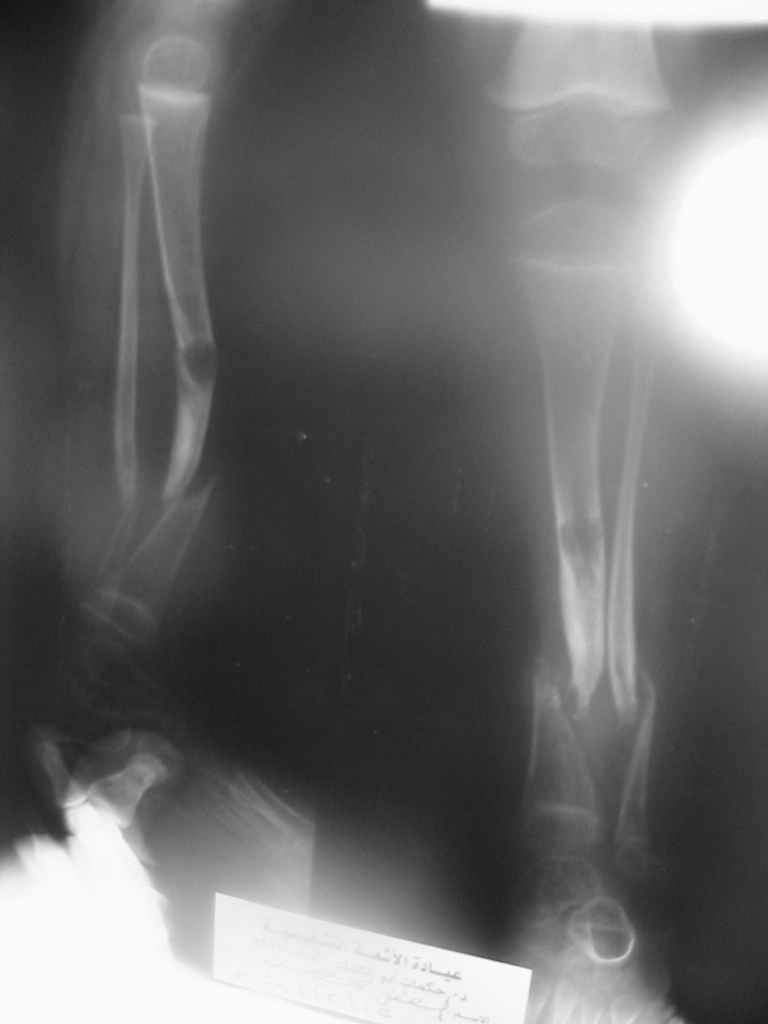

Uvazaemie Kollegy,Ko mne obratilsa malchik dva s polovenoi goda, stradaet ot vrozdennogo loznogo sustava N-3 kostei goleny,

А почему нейрофиброматоз? По представленной рентгенограмме определяется перестройка костной ткани берцовых костей, соответствующая системному заболеванию костной ткани - фиброзной дисплазии, предлагаемое И.Г. Лагуновой название данной нозологической формы - "диспластическая ангуляция голени". Изменения концов костных фрагментов протекают по типу нейротрофического остеолиза, возникающего, как считается, вторично, на фоне деформации голени. Этим объясняют особенности зоны перестройки и отсутствие репарации при хирургической коррекции. Применяемый термин "врожденный псевдоартроз голени" не отражает сущности процесса - торможения развития всех компонентов диафиза на этапе закладки первичных мезенхимальных зачатков. То есть оставшаяся вне зоны дефекта костная ткань так же неполноценна и срастить ее с трансплантатом будет проблематично.

Diagnos Neurofibromatosis, byl postavlen etomu rebenku davno, ne tolko na osnovanii rentgenologicheskoi kartiny kostei goleny, no i na osnovanii nalichiya ryada drugih priznakov i projiavlenii zabolevaniya, v t.ch. piatna "cafe-au-lait spots", i neurofibromatoznie uzly pod kozhei, i nasledstvenny anamnesis, i, nakonets, vrozdenny pseudoartrosis "to chto Vi vidite na snimkah", vot pochemu ne stavili Vash diagnos.

A chto kasaetsa Termina vrozdenny pseudoartros, to ortopedy ego ispolziot dla oboznachenjia riada pohozheih sostianii, nezavisimo ot prichiny vozniknovenjia etogo sostianiya!